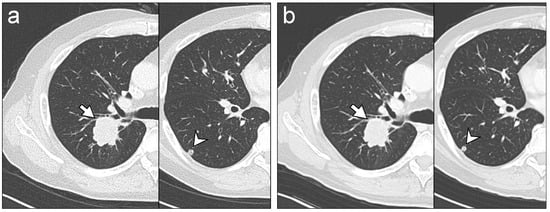

| Lung metastasis | 89 [8/9] | 100 [35/35] | 98 [43/44] | 0.94 | 100 [9/9] | 100 [35/35] | 100 [44/44] | 1.0 | 0.59 | 0.66 |